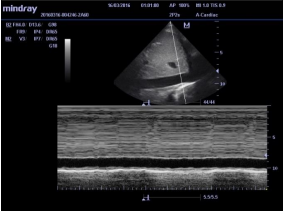

Avaliação do diâmetro veia cava inferior